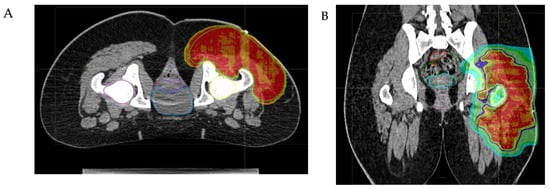

- The physical properties of protons allow for a significant escalation in dose, potentially up to approximately 60 Gy Relative Biological Effectiveness (RBE), in the treatment of radioresistant histotypes, such as Malignant Peripheral Nerve Sheath Tumors (MPNSTs) (see Figure 3).